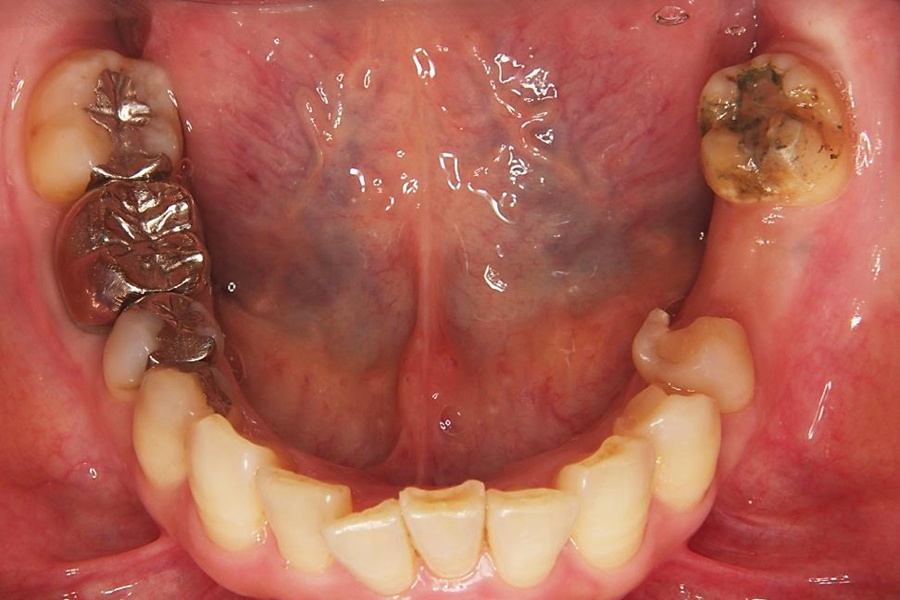

| 症状 | 奥歯のブリッジが取れてしまって食事がしにくい |

| 原因 | ブリッジ下の2次カリエス(虫歯の再発) 咬み合わせの不調和による咬合力の不均衡 |

| 治療法 | 矯正治療 自家歯牙移植 メタルボンドセラミッククラウン |